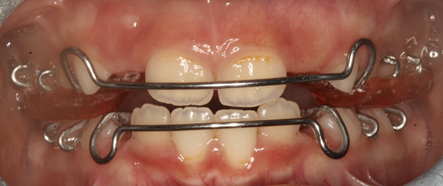

Se tuvo una conversación sobre el comportamiento de la paciente con su acudiente en caso de que se tuviera que colocar aparatología ortodóntica removible. Se llega a la conclusión de colocar dos aparatos: Hawley superior modificado con tornillo de expansión, planos de altura y flechas y Hawley inferior modificado con flechas y helicoides. (2,3)

Figura 11. Vista de Hawley frontal